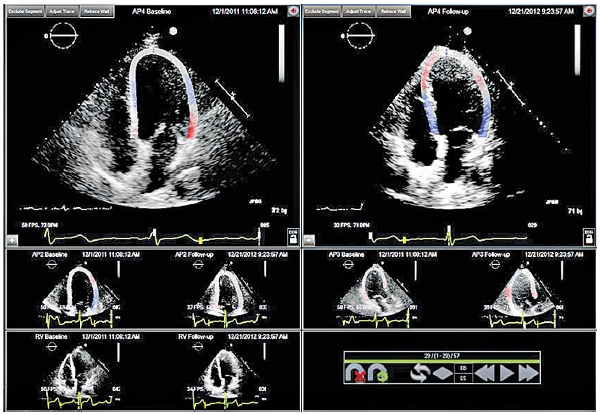

Noi am lucrat printr-o teză de doctorat (Dr. Anca Maria Popară-Voica) la „determinarea efectelor toxice ale chimioterapiei asupra cordului”.

Concluziile studiului nostru se referă la necesitatea monitorizării active a pacienţilor ecografici care primesc tratament antiangiogenic şi a colaborării strânse oncolog-cardiolog.

Tratamentul antiangiogenic induce la jumătate din pacienţi agravarea HTA preexistentă şi apariţia HTA de novo plus reducerea parametrilor de funcţie sistolică a ambilor ventriculi.

Totuşi disfuncţia cardiacă trebuie privită ca o consecinţă a toxicităţii miocardice intrinseci a terapiei in discuţie, HTA preexistentă fiind factorul permisiv/precipitant major al cardiotoxicității acestei terapii.